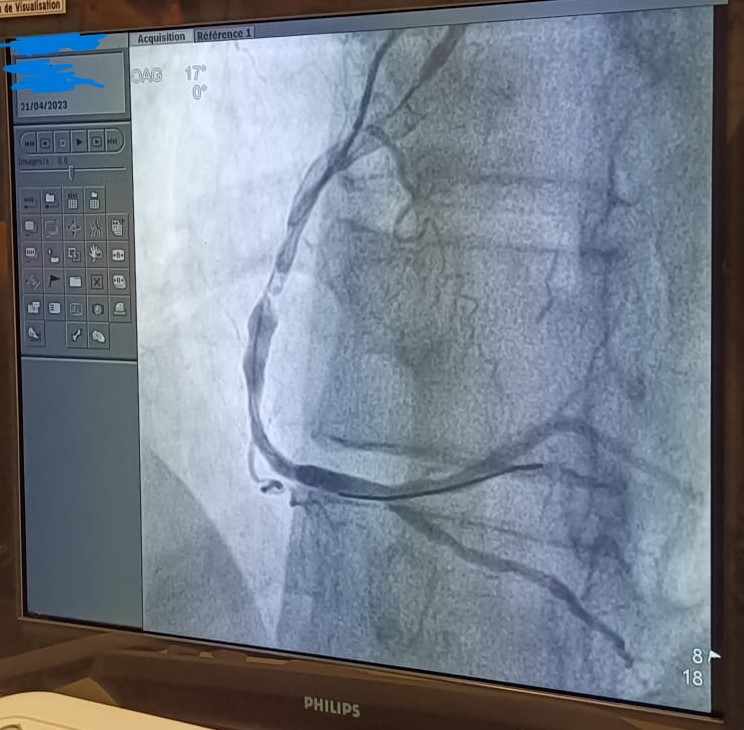

Unsurprisingly, an occluded RCA, featuring multilevel lesions.

Both the thrombo-aspiration and the angioplasty are successfull.

(The LCA is not unscathed, and will probably need a deferred intervention).